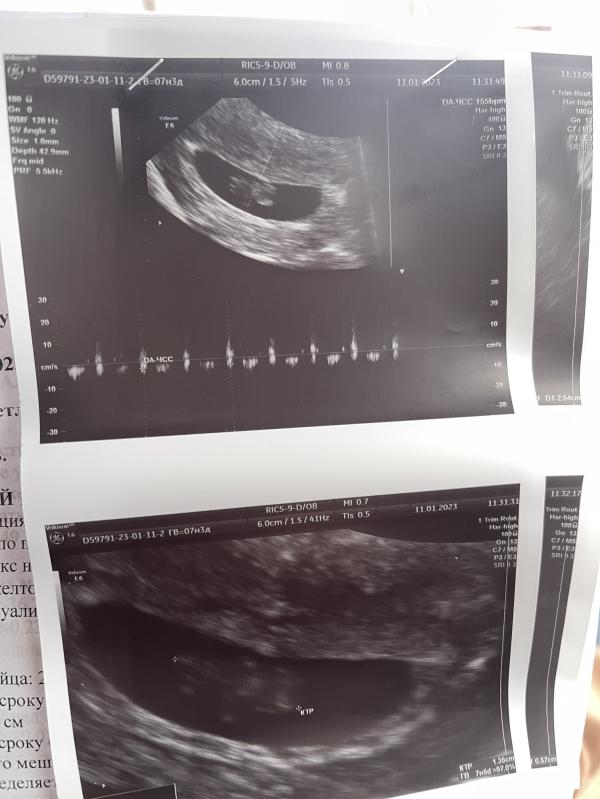

27.12 поехала на первое узи (узнала, что беременность маточная) было 5 недель.

11.01 второе узи (посмотрели сердцебиение малыша) все хорошо 🙏🏼 по переживала безумно. Когда увидела на Узи как бьется сердечко, не произвольно слезы потекли от счастья 💛